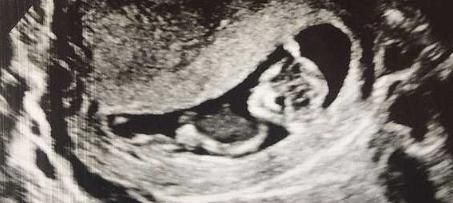

而事情的转折发生在吉文斯之后的孕检,当她查看B超影像的时候发现两个胎儿的发育差了很多,医生也遗憾的告诉她目前只能听到一个胎心音,吉文斯不能接受这个检查结果,又反复去其他医院检查,可最终结果都是一样的。

而在怀孕第13周的时候,医生正式告诉吉文斯超声影像显示肚中只有一个胎儿了,另一个胎儿已经把死去的胎儿吸收了。吉文斯收到这个通知非常的难过和伤心,悲痛了好几天还为这个“消失”的胎儿取了名字作纪念。

没想到肚子里存活的这个胎儿健康的生出来了,是个男宝宝,并且腿上的膝盖处有一个形状很特殊的胎记,吉文斯发现这个胎记很像之前另一个胎儿的B超影像,也就是陪伴了他好几周最后被他吸收的姐姐。